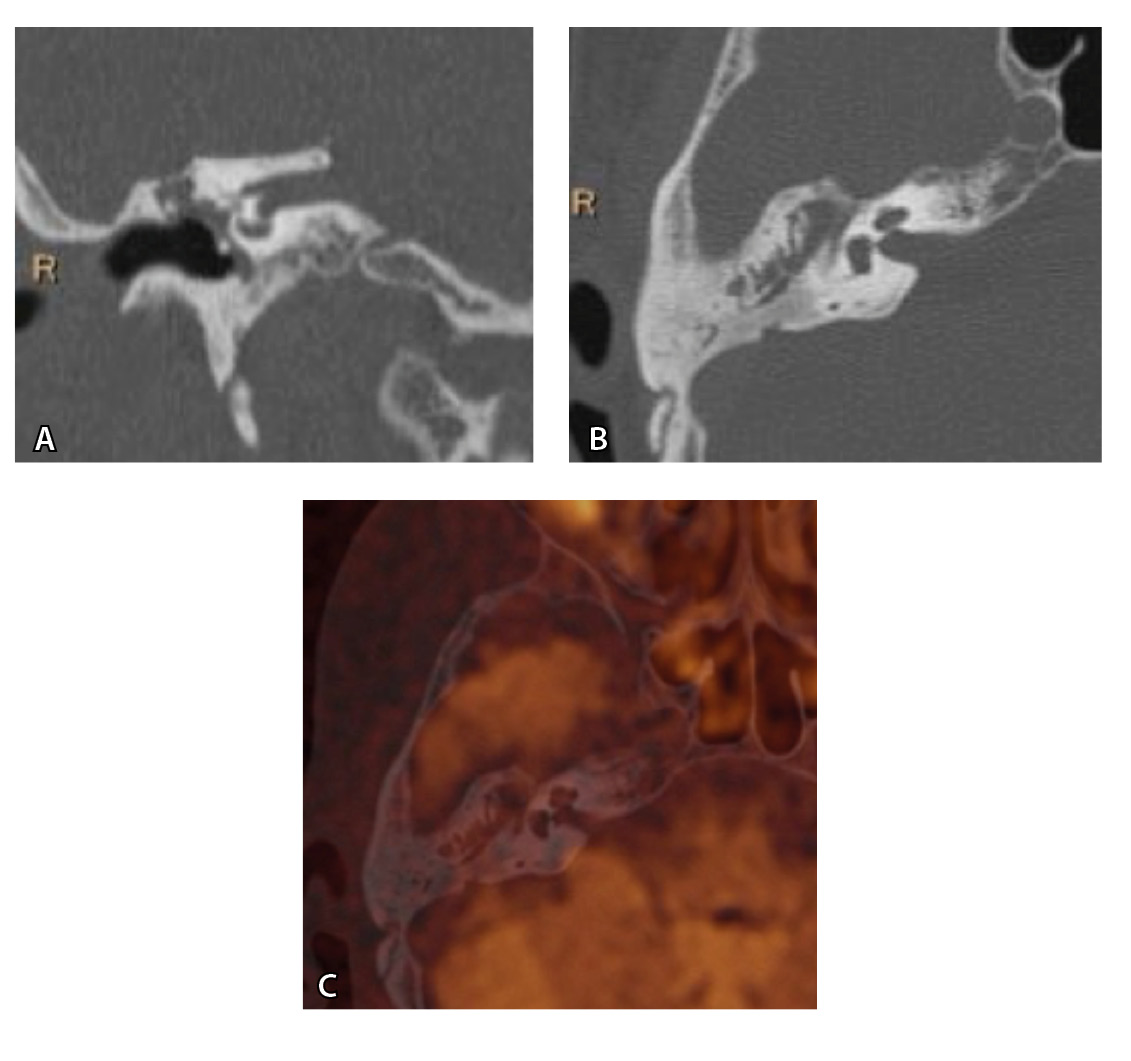

Рис. 4. При компьютерной томографии (КТ) визуализируются признаки хронического гнойного среднего отита справа. Наблюдаются латерализация косточек среднего уха и узурация их по имедиальной поверхности на уровне эпитимпанума (тело наковальни и головка молоточка) – классические КТ-признаки холестеатомы натянутой части барабанной перепонки (А, Б). Однако по данным магнитно-резонансной томографии (В) и в последующем при оперативном лечении холестеатома не подтверждена